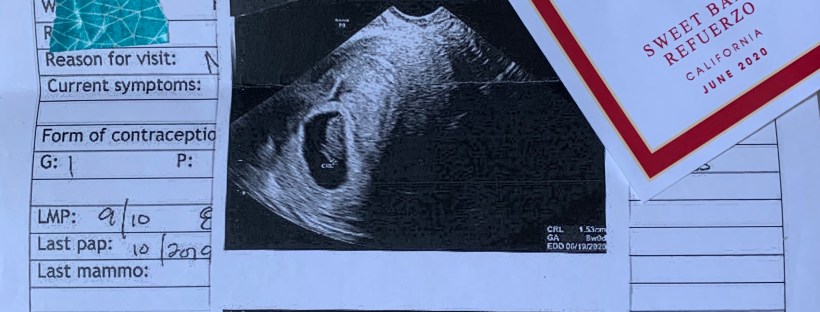

Fast forward four weeks later, (which meant I was already eight weeks pregnant) and I had my first OB appointment. This would also be my first ultrasound. Prior to the appointment, I felt better. Less tired and I was really taking good care of myself. I had no inkling of a miscarriage happening. When we heard no heartbeat and when we saw my doctor’s face look a little sad, we just knew we lost the baby. It was one of the saddest feelings ever. A feeling that lingers and stays with you.